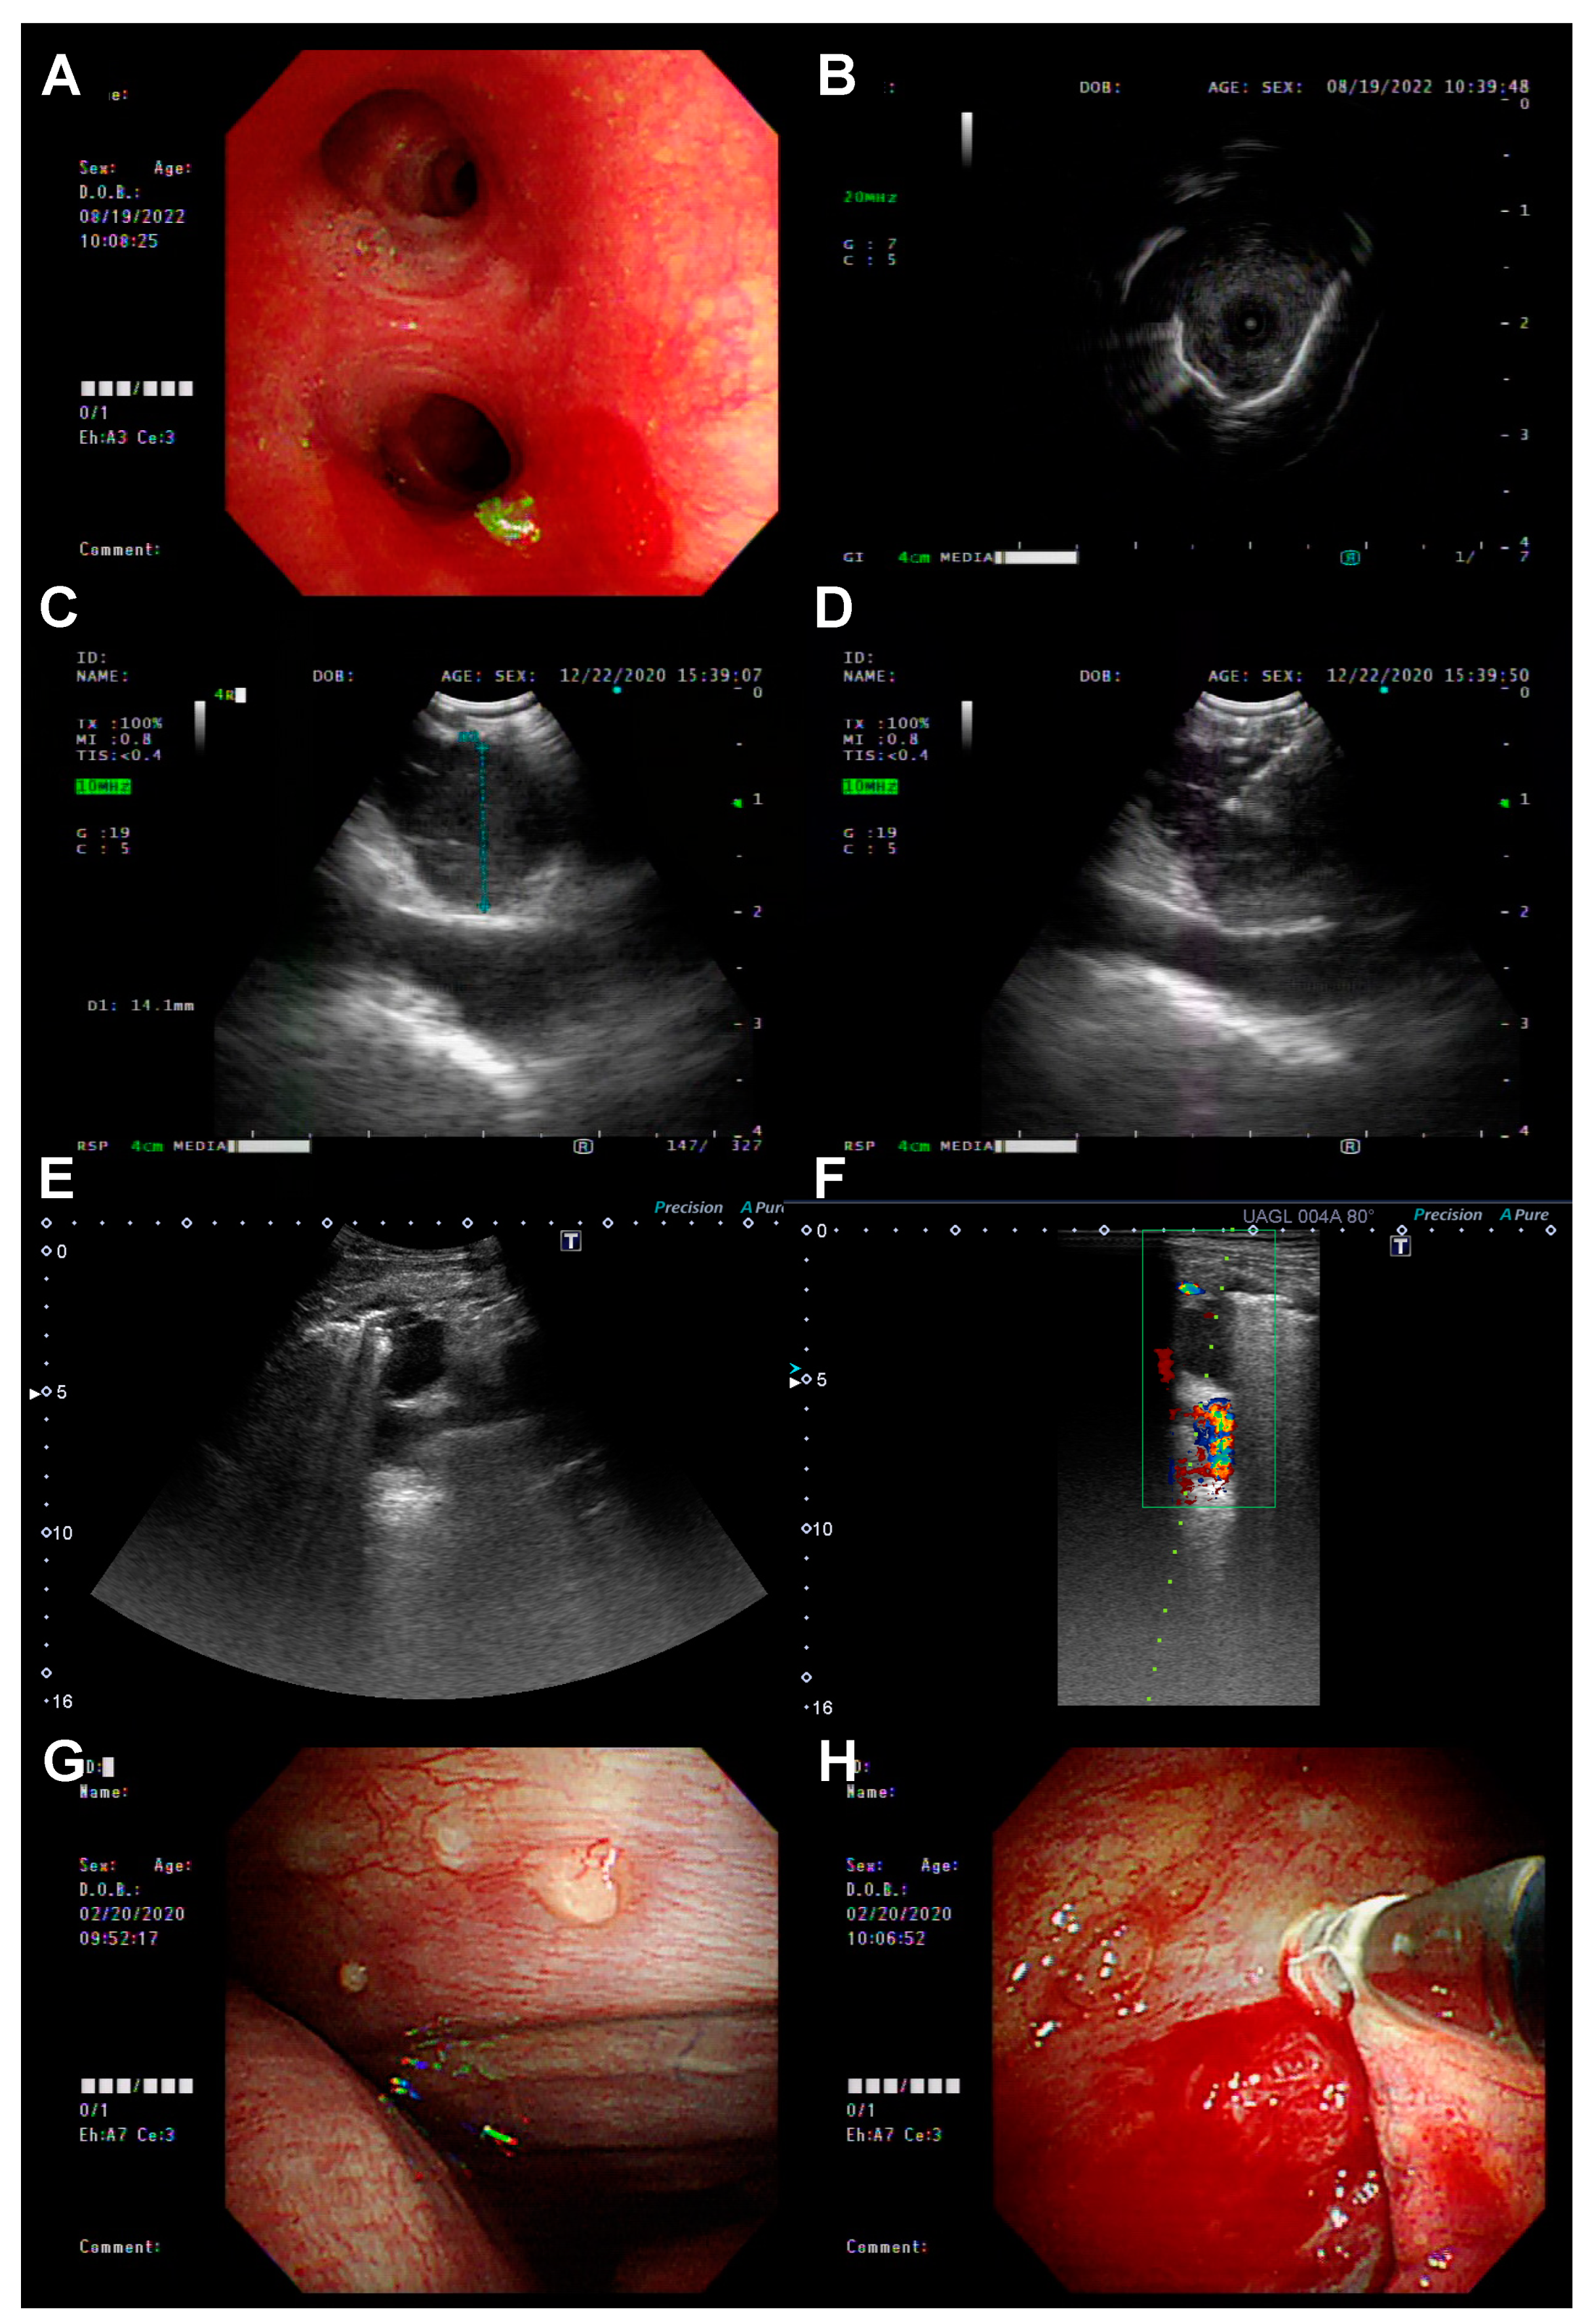

Patients were diagnosed with advanced or metastatic EGFR-positive NSCLC at the initial biopsy, i.e., biopsy at the time of diagnosis. Re-biopsy was defined as a subsequently performed biopsy to screen for the acquired resistance mechanism (the T790M mutation) after the failure of any line of anti-cancer treatment. The first re-biopsy was defined as the biopsy performed for the first time after the failure of the first-line EGFR-TKI treatment, the second re-biopsy as the re-biopsy performed after the first re-biopsy, and so on. The biopsy procedures included IP methods (Figure 1)—bronchoscopy with radial probe-EBUS (R-EBUS), EBUS-TBNA, sono-guided biopsy, and medical pleuroscopy—as well as non-IP methods—CT-guided biopsy and surgery.

Figure 1. The biopsy procedures included IP methods: (A,B) Bronchoscopy with radial probe-EBUS (R-EBUS); (C,D) EBUS-TBNA; (E,F) sono-guided biopsy; and (G,H) medical pleuroscopy.